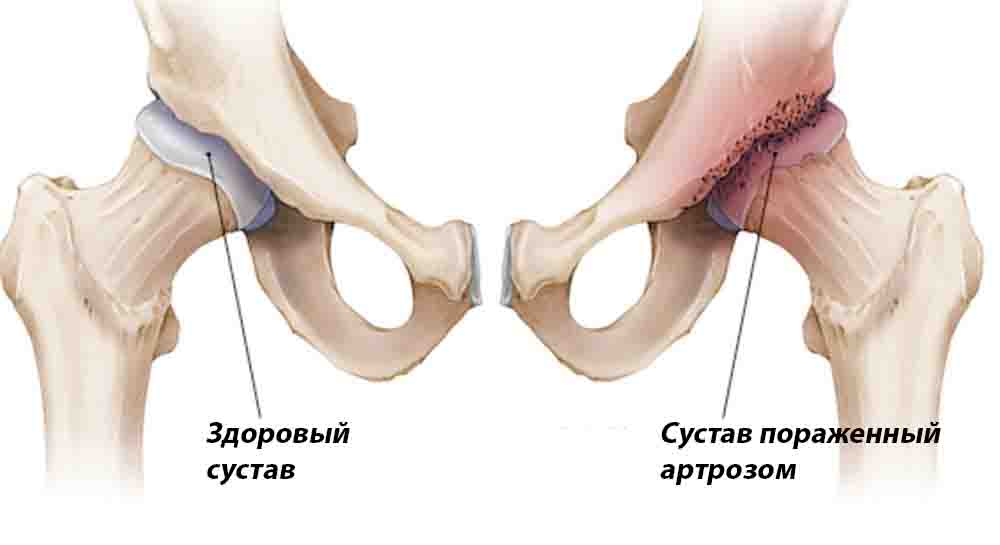

Фотографии и схемы: Коксит правого тазобедренного сустава